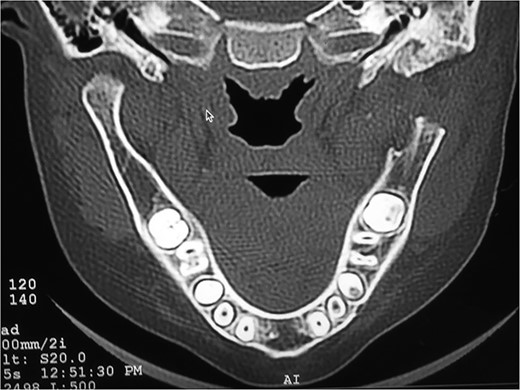

RADIOGRAPHIC FEATURES

Orthopantomogram and computed tomography (CT) scan with 3D reconstruction revealed a lack of structural organization and obliteration of right TMJ space. The right body of mandible was arch shaped due to restriction of the right condyle with right coronoid pushing upwards. There was also occlusal cant on frontal CT scan. Coronal view of CT scan demonstrated ankylotic mass. Based on these finding, a diagnosis of unilateral bony ankylosis of TMJ on right side was confirmed (Fig. 3).